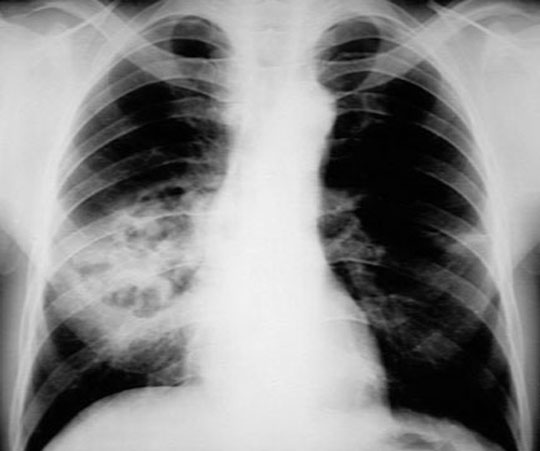

Bronchopneumonia: Note patchy infiltrates

Case 2 CXR: Lateral showing patchy infiltrates